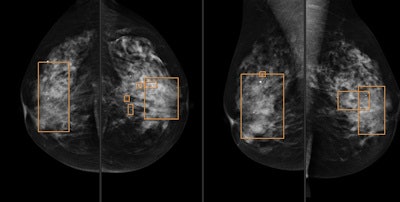

A 62-year-old woman with invasive ductal carcinoma 11 mm in size. Above: Plain digital mammography with a focal asymmetry in left breast. Below: CAD correctly detected the lesion. All images courtesy of Dr. Xavier Bargalló.Prospective study

The prospective study included data from 21,321 consecutive screening mammograms (Senographe 2000D, GE Healthcare) in incident rounds (2010-2012). Exams were interpreted in a protocol that included single reading plus CAD (SecondLook, Premier, iCAD). These studies were then compared with data from 47,462 consecutive screening mammograms in incident rounds (2004-2010) that were interpreted following a protocol with double reading plus arbitration.

For the single reading, radiologists were selected based on their previous performance, according to the authors. They read the mammograms and made a decision whether to recall the patient, at which point the CAD marks were engaged. The radiologists then revised the marks and made a final decision.